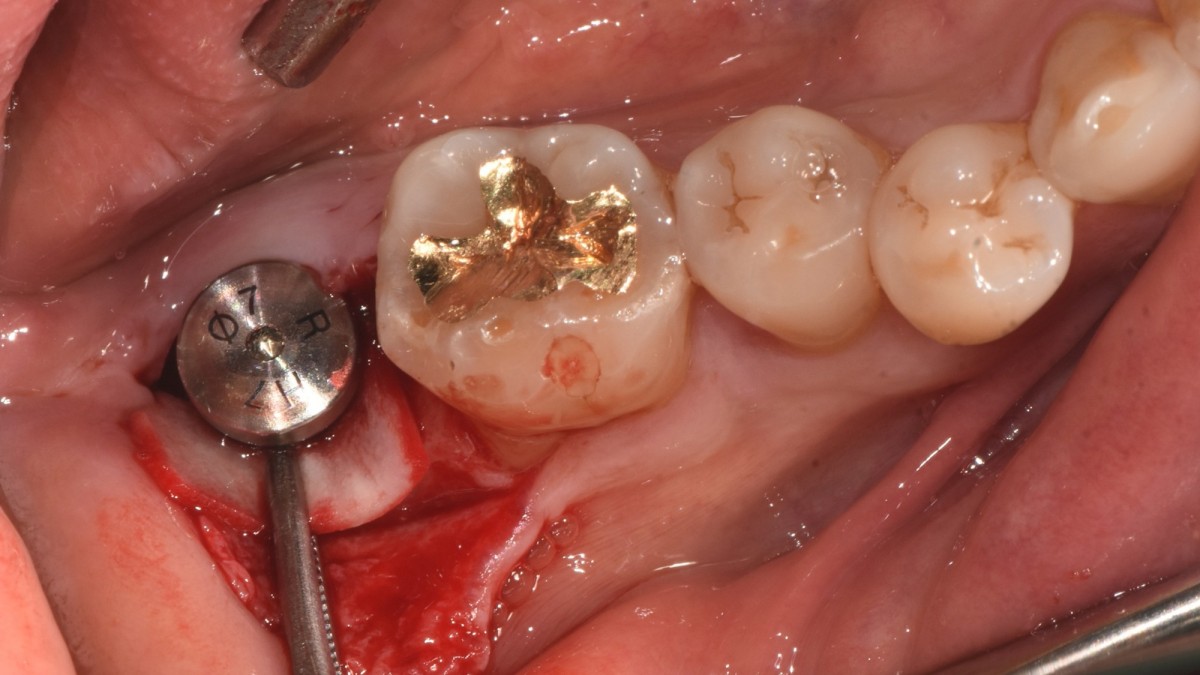

▲torque value after insertion

▲Arum Dentistry NB1 5*10